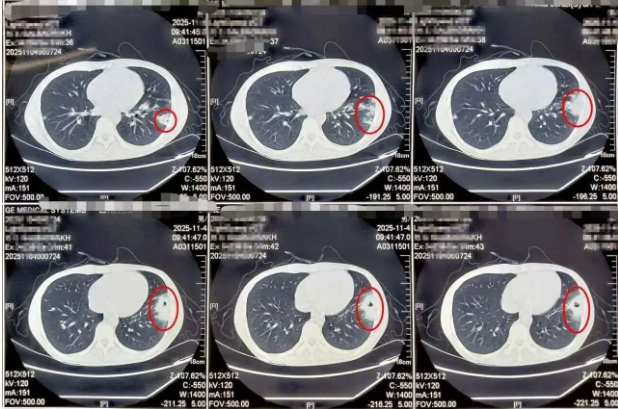

11月11日,CALBADRARH来到北京天坛医院呼吸与危重症医学科就诊,面对这位辗转两个国家多家医院仍未能找到病因的患者,呼吸科诊疗团队立即组织全科讨论,对患者长达几个月的病史进行抽丝剥茧的分析。在梳理病情时,诊疗团队发现,患者病情的转折发生在当地治疗期间深静脉置管和血液净化之后,而通过病原学宏基因组学检测技术,团队在患者的血液和肺泡灌洗液中都发现了耐甲氧西林金黄色葡萄球菌(MRSA),患者胸部CT显示的双肺多发空洞,也正是诊疗团队初步判断,很可能是患者抵抗力低,有创操作后继发感染。